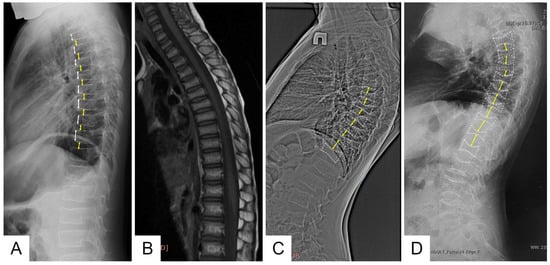

Figure 2. Lateral views of the thoracic and upper lumbar spine of the patients of different ages: radiograph of the 6 y.o. boy (F1 III-4) (A)—decreased height and anterior wedging of the vertebral bodies (white arrows), increased height of intervertebral discs (black arrows); T1-weighted MRI of the same patient of the 4 y.o. (B); radiographs of the 12 y.o (F2 II-4) (C) and 30 y.o. (F3 II) (D) patients—severe platyspondyly with accentuated biconcave shape of the vertebral bodies (white dotted lines) and increased height biconvex intervertebral disks (black arrows) more prominent at the thoracic level.

Family 1 is Belarusian and has five affected members in three generations. Proband (III-4) is a 6-year-old boy who started to complain (pointed to where it hurt) of lower back pain from the age of 1 year 7 months, according to his parents. This pain usually lasted from 2 weeks to 1 month and limited the patient’s physical activity, as he was afraid to walk the stairs. Taking into account the increasing lower back pain, an MRI of the thoracolumbar spine was performed at the age of 4 years, which revealed signs of compression fractures of the C7, Th 2-8 vertebral bodies (Figure 2).

Control X-ray densitometry at the age of 6 showed positive dynamics: the BMD of the lumbar spine was 0.357 g/cm2, Z-criterion was −1.9. An X-ray examination of the spine at the age of 6 years revealed diffuse rarefaction of the bone pattern of the vertebrae and a biconcave shape of the thoracic vertebral bodies (Figure 2).

According to the results of the densitometry, all affected family members were diagnosed with severe osteoporosis, and an X-ray examination of the spine revealed signs of compression fractures of the vertebral bodies (Figure 2).

An X-ray examination of the thoracolumbar spine revealed a biconcave appearance of the vertebrae and a wedge-shaped deformity of the vertebral bodies at the entire level of the thoracolumbar spine (Figure 2). During bone scintigraphy of the skeletal system in a 30-year-old individual, no metabolically active zones were detected, which are often found in patients with osteogenesis imperfecta, even outside fracture zones and bone calluses.